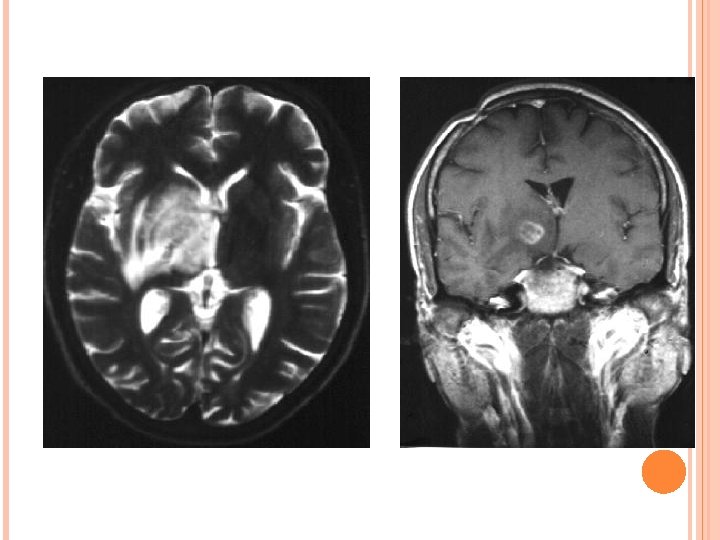

PRIMARY CNS LYMPHOMA • Usually Non-Hodgkin`s(B cell type) lymphoma • Location: Basal ganglia. Periventricular. Corpus callosum. • Presentation: Seizures, Headaches, Focal neurological deficit.

PRIMARY CNS LYMPHOMA IMAGING: CT-Typically a solitary hyperdense mass on NECT however multifocal in 50% cases. MR-Iso to hypointense on T 1 W and T 2 W image with diffusion restriction. Enhancement pattern are variable homogenous/heterogenous/ring like. Edema and mass effect in half of the lesion. Increase choline peak on MRS and increase Thallium uptake on SPECT.

Primary CNS lymphoma High choline peak. Lactate peak in necrotic component.